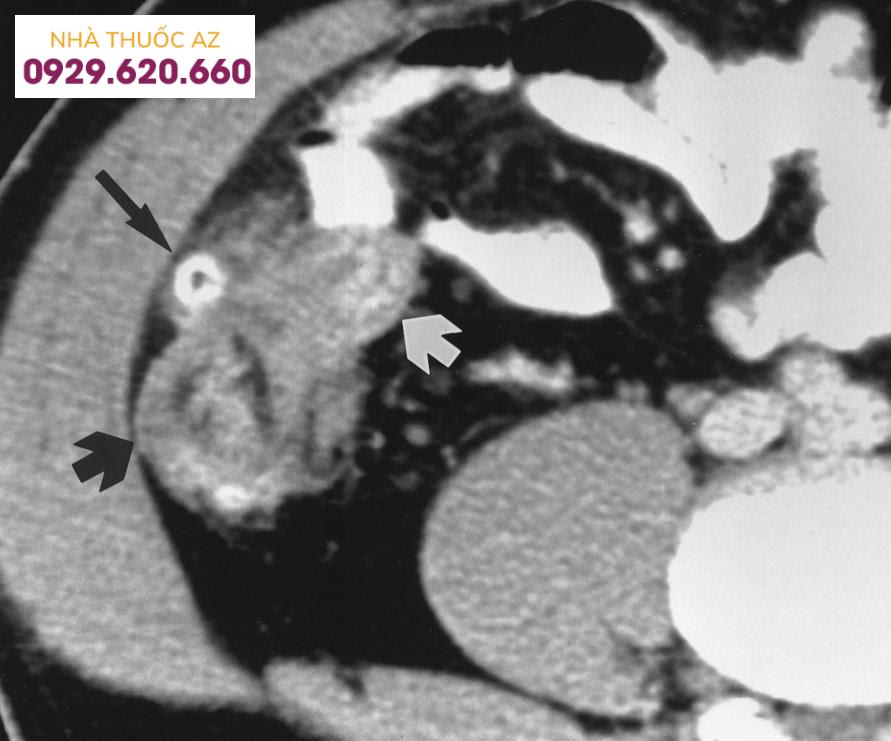

2. Chụp cắt lớp điện toán (CT)

CT có độ nhạy và độ đặc hiệu cao (97% và 100%), tỉ lệ dương giả thấp. Theo Hội các phẫu thuật viên đại trực tràng Hoa Kỳ, CT bụng chậu là phương tiện thích hợp nhất để khảo sát những trường hợp nghi ngờ VTTĐT. CT cung cấp rất nhiều thông tin giúp cho chẩn đoán chính xác, phát hiện biến chứng (áp xe, rò tiêu hóa, tắc ruột), đánh giá khả năng can thiệp nội hay ngoại khoa, và theo dõi hồi phục.

Các tiêu chí chính chẩn đoán viêm túi thừa đại tràng trên CT là:

Dày thành ĐT (thành dày ≥ 4mm) chiếm 70%.Hình ảnh túi thừa chiếm 84%.Thay đổi (tăng) mật độ mô mỡ quanh ĐT chiếm 98%.Hình ảnh áp xe (các ổ tụ dịch quanh ĐT) chiếm 35%.

Hình ảnh CT của viêm túi thừa manh tràng (Nguồn: Jang H.J., et al. (2000), “Acute diverticulitis of the cecum and ascending colon: the value of thin-section helical CT findings in excluding colonic carcinoma”, AJR Am J Roentgenol, Vol.174 (5), p.1397-1402)

Phân độ viêm túi thừa đại tràng trên hình ảnh CT scan:

Nhẹ: Thành đại tràng xích ma dày <5mm, phản ứng viêm của mô mỡ quanh đại tràngNặng: Áp xe, Khí ngoài lòng đại tràng

CT phát hiện chính xác những trường hợp VTTĐT có biến chứng như VPM (hình ảnh dịch và hiện tượng viêm lan tỏa), các thể rò tiêu hóa (hình ảnh gián tiếp như hơi hay chất cản quang từ lòng đại tràng đọng ở bàng quang, âm đạo, thành bụng; hình ảnh đường rò trực tiếp hiếm khi thấy), và tắc ruột (hình ảnh các quai ruột giãn với hơi và dịch, dày thành đại tràng đoạn tắc).

CT giúp phân độ bệnh chính xác theo phân độ Hinchey trong 90% trường hợp. Ambrosetti cũng đưa ra bảng phân độ nặng của VTTĐT dựa trên hình ảnh CT. Phân độ bệnh chính xác giúp lựa chọn bệnh nhân để điều trị bảo tồn hay phẫu thuật. Điều trị bảo tồn ở những bệnh nhân viêm túi thừa nặng có tỷ lệ thất bại cao và tăng nguy cơ có biến chứng thứ phát nếu điều trị không thành công.